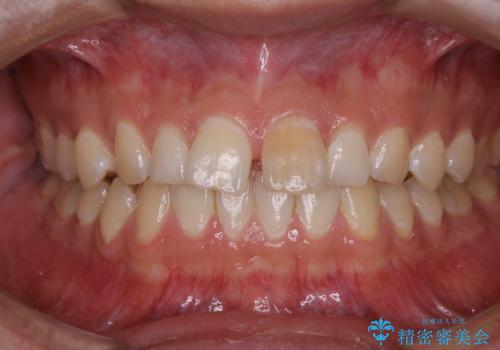

- 矯正治療を考えていて、歯科医院が久しぶりのためまずはクリーニングしたいとのことでした。PMTC60分コースを行いました。

矯正治療中は虫歯や歯周病リスクが高くなることがあります。

インビザライン矯正治療はマウスピースで1日20時間以上歯列全体を覆っているため、歯石や汚れなどが付着したままだと、フィットが悪くなったり、口臭が強く出たりする原因につながることもあります。